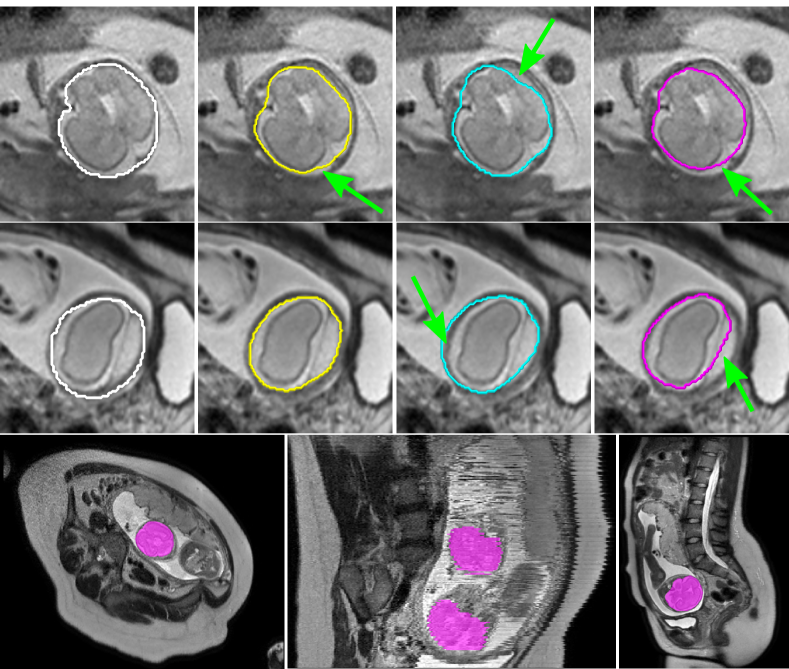

Refer to caption

Figure 3: Top and middle row: Example results of expert manual (white), expert fully supervised (yellow), expert weakly supervised (cyan) and non-expert weakly supervised segmentations. Prediction errors are marked with arrows (green). Bottom row: Non-expert weakly supervised segmentation results on axial and sagittal slices, including twins (middle).

Table I shows the accuracy as DSC for all compared approaches, respectively. While learning under full expert supervision exhibits the most accurate performance, using weakly supervised simulated expert annotations and weak annotations from non-expert raters yield comparably high results. Figure 3 shows selected examples of segmentation results and segmentation errors for all compared methods.

All compared methods perform well in qualitative comparison with other studies employing highly targeted, fully supervised approaches. The works in [16], [17] and [18] reported mean DSC scores of 93.0%, 90.7% and 80.4%, respectively. Note, that the FCN prediction could additionally be post-processed with a graphical method, which has been shown to improve results in other segmentation problems [2, 3]. As expected, a higher accuracy could be achieved when learning under full supervision, however differences appear marginal compared to those reported using bounding box annotations [2, 3]. Surprisingly, both weakly supervised networks present with very similar accuracy (see Tab. I), when random factors such as sampling and augmentation are accounted for. Particularly interesting is the presentation of learned segmentation errors. We expect the exclusion of the cerebro-spinal fluid when using non-expert annotations (c.f. Fig. 3, magenta) is due to differences in image interpretation of the crowd on where the brain boundary is on axial slices. Similarly, the oversegmentation of the skull (c.f. Fig. 3, cyan) might be due to systematic oversegmentations from computed expert super-pixels. Systematic annotation errors could be addressed by integration of quality assurance measures and/or annotation regularisation post collection. Considering the base accuracy of the collected fetal brain annotations from non-experts, we observe similar performance to that of an expert (c.f. Fig. 4), indicating that some anatomical annotation tasks can be performed by crowds with less expertise.